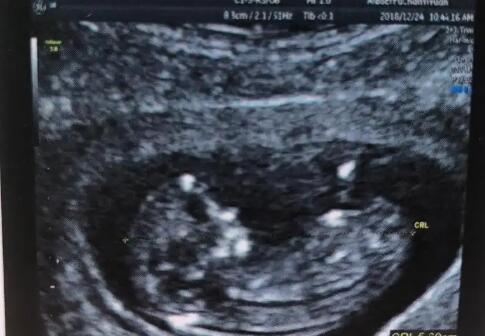

南寧市做試管嬰兒的價(jià)格 2022年南寧可以包生男生試管醫(yī)院分享 ‘彩超下的男孩